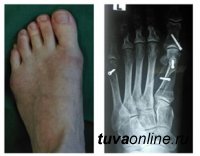

Нашими травматологами внедрены корригирующая остеотомия при деформациях переднего отдела стопы, а также остеосинтез лучевой кости пластиной с угловой стабильностью.